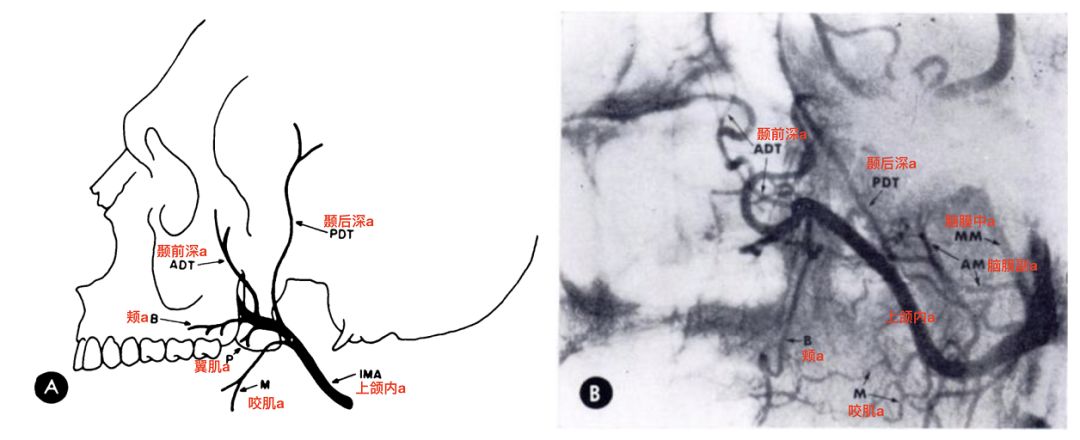

上颌内动脉第二段(翼段)及其分支模式图(Allen 1973)。

![]()

上颌内动脉第二段分支包括:颞深动脉,咬肌动脉,颊动脉,翼肌动脉等。第二段的分支以肌肉的分支为主。

上颌内动脉第二段主要分支(Alvernia 2017)。

4、上颌内动脉第二段的分支包括颞深动脉,咬肌动脉,颊动脉,翼肌动脉等。